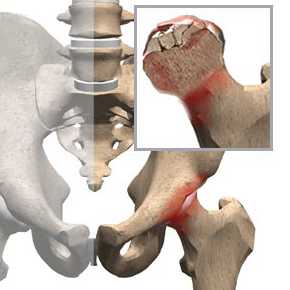

- Асептический некроз тазобедренного сустава

При этом заболевании разрушается головка бедренной кости, которая страдает от нехватки кислорода. Это может привести к серьёзным осложнениям – гангрене и ампутации конечности. Причины – чрезмерная нагрузка на сустав, нарушения в организме или предрасположенность.

При остеонекрозе в области тазобедренного сустава дислокация боли происходит непосредственно около паха и передается на ягодицы и бедра. Происходит ограничение подвижности, со временем появляется хромота. Сложным заболеванием считается асептический некроз головки бедренной кости.

Асептический некроз кости – это хроническая болезнь, которая вызвана нарушением кровоснабжения костной ткани. По мере развития некроза происходит разрушение ткани. Чаще всего некроз развивается в области головки кости в месте сочленения с суставом. Страдают от недуга крупные кости.Чаще у больных развивается асептический некроз головки бедренной кости в области тазобедренного сустава, но может быть поражение головки таранной кости в области голеностопного сустава и головки плечевой кости в области плечевого сустава. Поражает заболевание и взрослых людей, и детей. У детей некроз протекает в более легкой форме, лечение болезни оказывается более эффективным. Асептический некроз могут вызвать различные факторы, но все они приводят к нарушению кровотока в мелких сосудах кости и питания клеток.

Чаще всего страдает бедренная кость, но может развиваться и асептический некроз таранной кости, плечевой кости и других. Заболевания локализуется возле крупных суставов: тазобедренного, голеностопного, коленного, плечевого.

В некоторых случаях асептический некроз головки бедренной кости развивается у детей, чаще у мальчиков до семи лет. В этом случае болезнь характеризуется более легким течением, и выздоровление наступает быстрее.При этом заболевании происходит нарушение кровотока в кости и питания клеток костной ткани. Это приводит к гибели остеоцитов и остеобластов, которые вырабатывают межклеточное вещество и обеспечивают рост кости. Активность остеокластов при этом может увеличиться, и процесс разрушения костной ткани усиливается.

Вследствие этого уменьшается прочность кости. Нагрузки на такую кость приводят к повреждениям и переломам перекладин костной ткани, обломки которых сдавливают кровеносные сосуды и еще больше нарушают питание костной ткани. При этом происходит гибель клеток, и развивается некроз. Локализуется патология в местах наибольшего давления на кость, то есть, в головке кости вблизи голеностопного, плечевого или тазобедренного сустава.